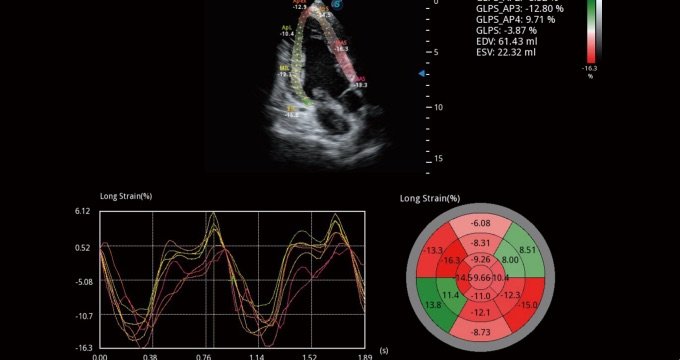

Quantitative Myokardanalyse (MQA)

MQA bietet eine präzise quantitative Messung der Myokardmechanik anhand einer empfindlichen Echtzeit-Verfolgung der Wandbewegung. Die Funktion erlaubt eine globale und regionale Abklärung einschließlich Dehnung, Dehnungsrate, Auslenkung, Geschwindigkeit usw.